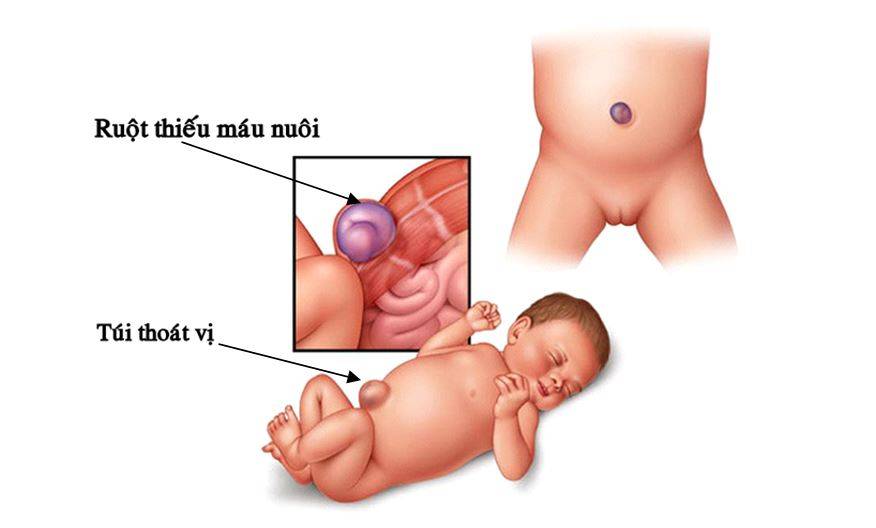

Чаще всего грыжа возникает вследствие дефекта передней брюшной стенки, слабости пупочного кольца. Провоцирующим моментом является длительное повышение внутрибрюшного давления в результате сильного кашля, запоров, продолжительного плача. Такие заболевания, как рахит, гипотрофия, снижающие тонус мышц, создают благоприятные условия для образования пупочной грыжи. Наиболее часто грыжа встречается у недоношенных детей. В пупочную грыжу обычно выпадают петли кишечника ребенка или сальника.

Образование врожденной грыжи. Как уже было сказано, поводом для образования грыжи является ослабление брюшной стенки. И существуют определенные причины, по которым ее формирование в утробе матери происходит не так, как это необходимо. А главной причиной слабости брюшины становится недостаточная прочность мышечной структуры и соединительных тканей — поэтому брюшина начинает развиваться с дефектами. В результате грыжевое образование возникает еще до рождения ребенка, ведь в утробе матери внутренние органы уже начинают оказывать давление на место соединения с пуповинным канатиком.

Пупочная грыжа у новорожденных может быть прямой или косой. В первом случае грыжевой мешочек и его составляющие просто выходят за пределы пупочного кольца. Во втором — возникает более сложная структура: грыжевой мешок сначала оказывается в просвете между поперечной фасцией и белой линией живота, а затем выводится в пупочное кольцо.

Схематическое изображение выпирания кишки в область пупка. Пупочная грыжа.

Схематическое изображение выпирания кишки в область пупка. Пупочная грыжа.